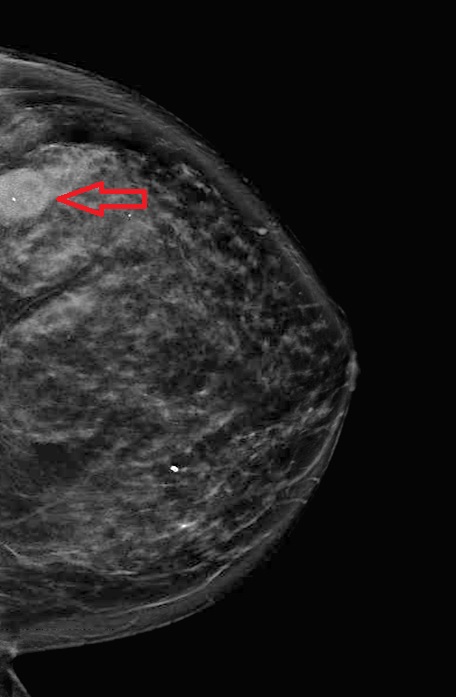

الحالة الأخيرة: كتلة صغيرة جدا في الثدي الأيسر. تم عمل رنين مغناطيسي واكتشاف انتشار للغدد اللمفاوية المجاورة. تم علاج المريضة واستئصال الكتلة والغدد بشكل كامل.